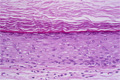

Macroscopic findings: Epidermal cyst is a cystic lesion that typically occurs on the face, neck, chest and back. It feels anchored on the skin surface with motility relative to surrounding tissues below the skin surface.